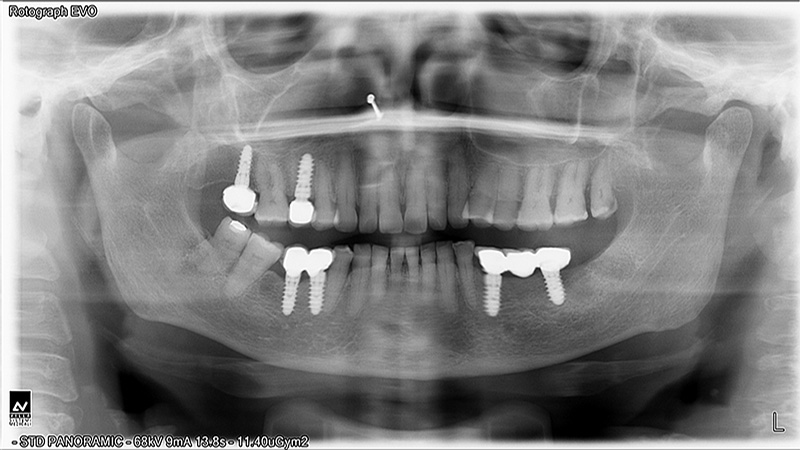

Implants

Implant Patients